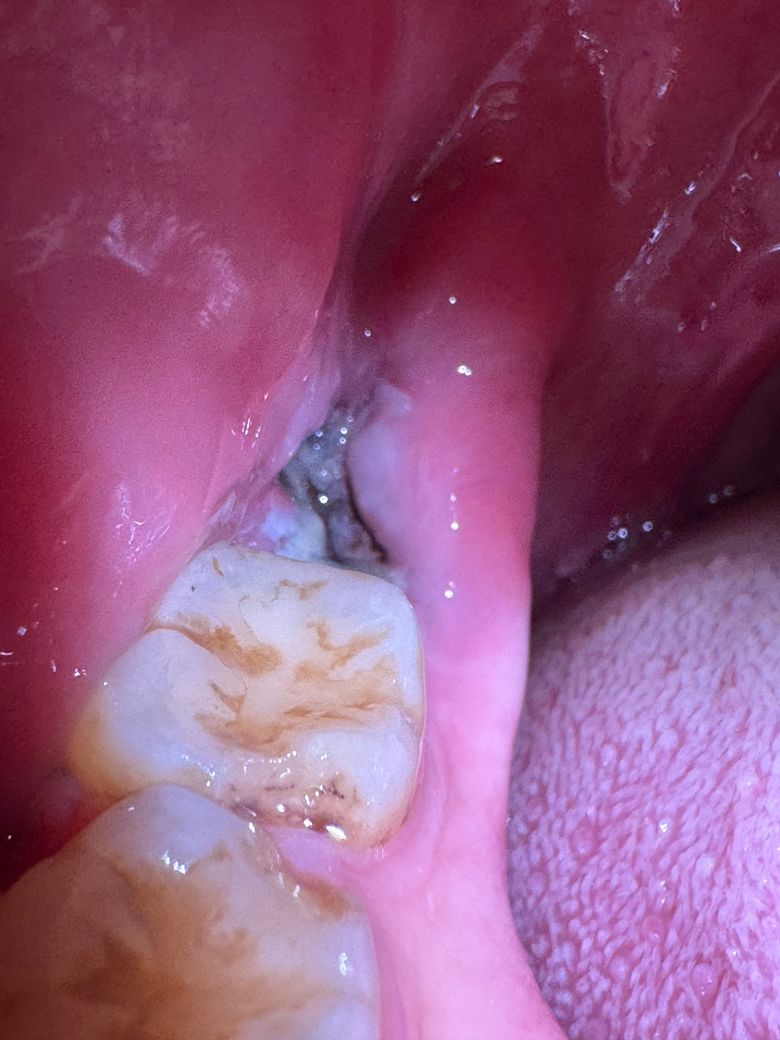

사랑니 발치 3일차, 혈병이 빠진건가요?

원래 붉은색이어야 하는걸로 아는데 이건 뭔가요? 음식물 섭취 뒤에 가글액 쏘아서 어느정도 빼냈는데 이건 뭔지 궁금합니다. 혈병이 빠진건가 걱정되서요

사진으로 봤을 경우에는 발치한 부위에 혈병이 잘 형성되어 있는 것으로 보입니다. 발치를 했다면 발치한 부위를 자극하지 않는 것이 좋습니다. 발치한 부위를 자극하게 되면 출혈이 되고 치유가 늦어질 수 있기 때문입니다.

원래 붉은색이어야 하는걸로 아는데 이건 뭔가요? -> 잇몸 치유 과정에서 생기는 부산물입니다. 혈병은 발치 후 1~2일차면 다 흡수되어 안보이는게 정상입니다.

사랑니를 발치한 이후에 회복되는 과정에서 하얀색의 막이 생기는 것은 정상적인 반응입니다.

지혈이 잘되고 잇몸이 아물고 잇는거 같습니다. 통증이 없다면 크게 걱정하지 않으셔도 됩니다.